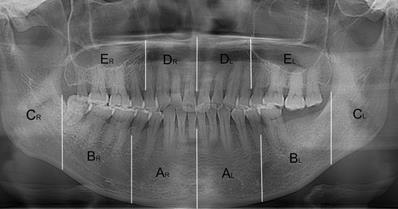

Figure 4

The resected regions in mandible and maxilla. AR/ AL: from the mandibular symphysis to the mental foramen; BR/ BL: from the mental foramen to the anterior of ramus; CR/ CL: the mandibular ramus. DR/ DL: from the incisive foramen to the medial wall of maxillary sinus; ER/ EL: the residual alveolar bone.

• For the osteosclerotic lesion, we resected the mandible and maxilla in ten regions and measured the radiodensity values of relevant regions which were comprehensively decided by the location of intraoral exposed bone and symptomatic areas (Fig. 1). The resected regions are stated as follows and showed in Figure 4. All CBCT slices in three views of a lesion were segmented according to the boundary of relevant regions and the average radiodensity values were calculated. (Mandible, AR/ AL: from the mandibular symphysis to the mental foramen; BR/ BL: from the mental foramen to the anterior of ramus; CR/ CL: the mandibular ramus. Maxilla, DR/ DL: from the incisive foramen to the medial wall of maxillary sinus; ER/ EL: the residual alveolar bone).